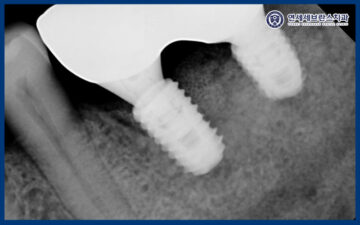

24.11.18

이렇게 잇몸치료가 전체적으로 마무리된 이후에는

본격적인 임플란트 식립을 진행하였습니다.

왼쪽 아래 치아의 경우 발치와 동시에

즉시 임플란트 식립을 시행하였으며,

전반적으로 치조골이 부족한 상태였기 때문에

임플란트의 초기 고정력과

장기적인 안정성을 확보하기 위해

뼈이식을 동반하여 식립을 진행하였습니다.

이를 통해 임플란트가

보다 단단하게 자리 잡을 수 있는

기반을 형성하고, 이후 보철 단계까지

안정적으로 이어질 수 있도록

치료를 계획하였습니다.